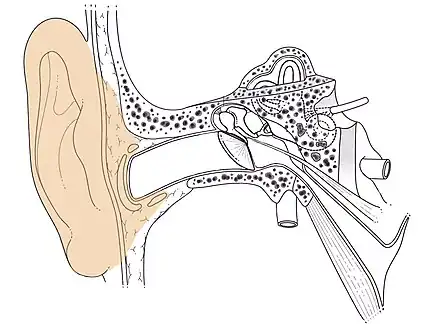

L'oreille externe : pavillon.